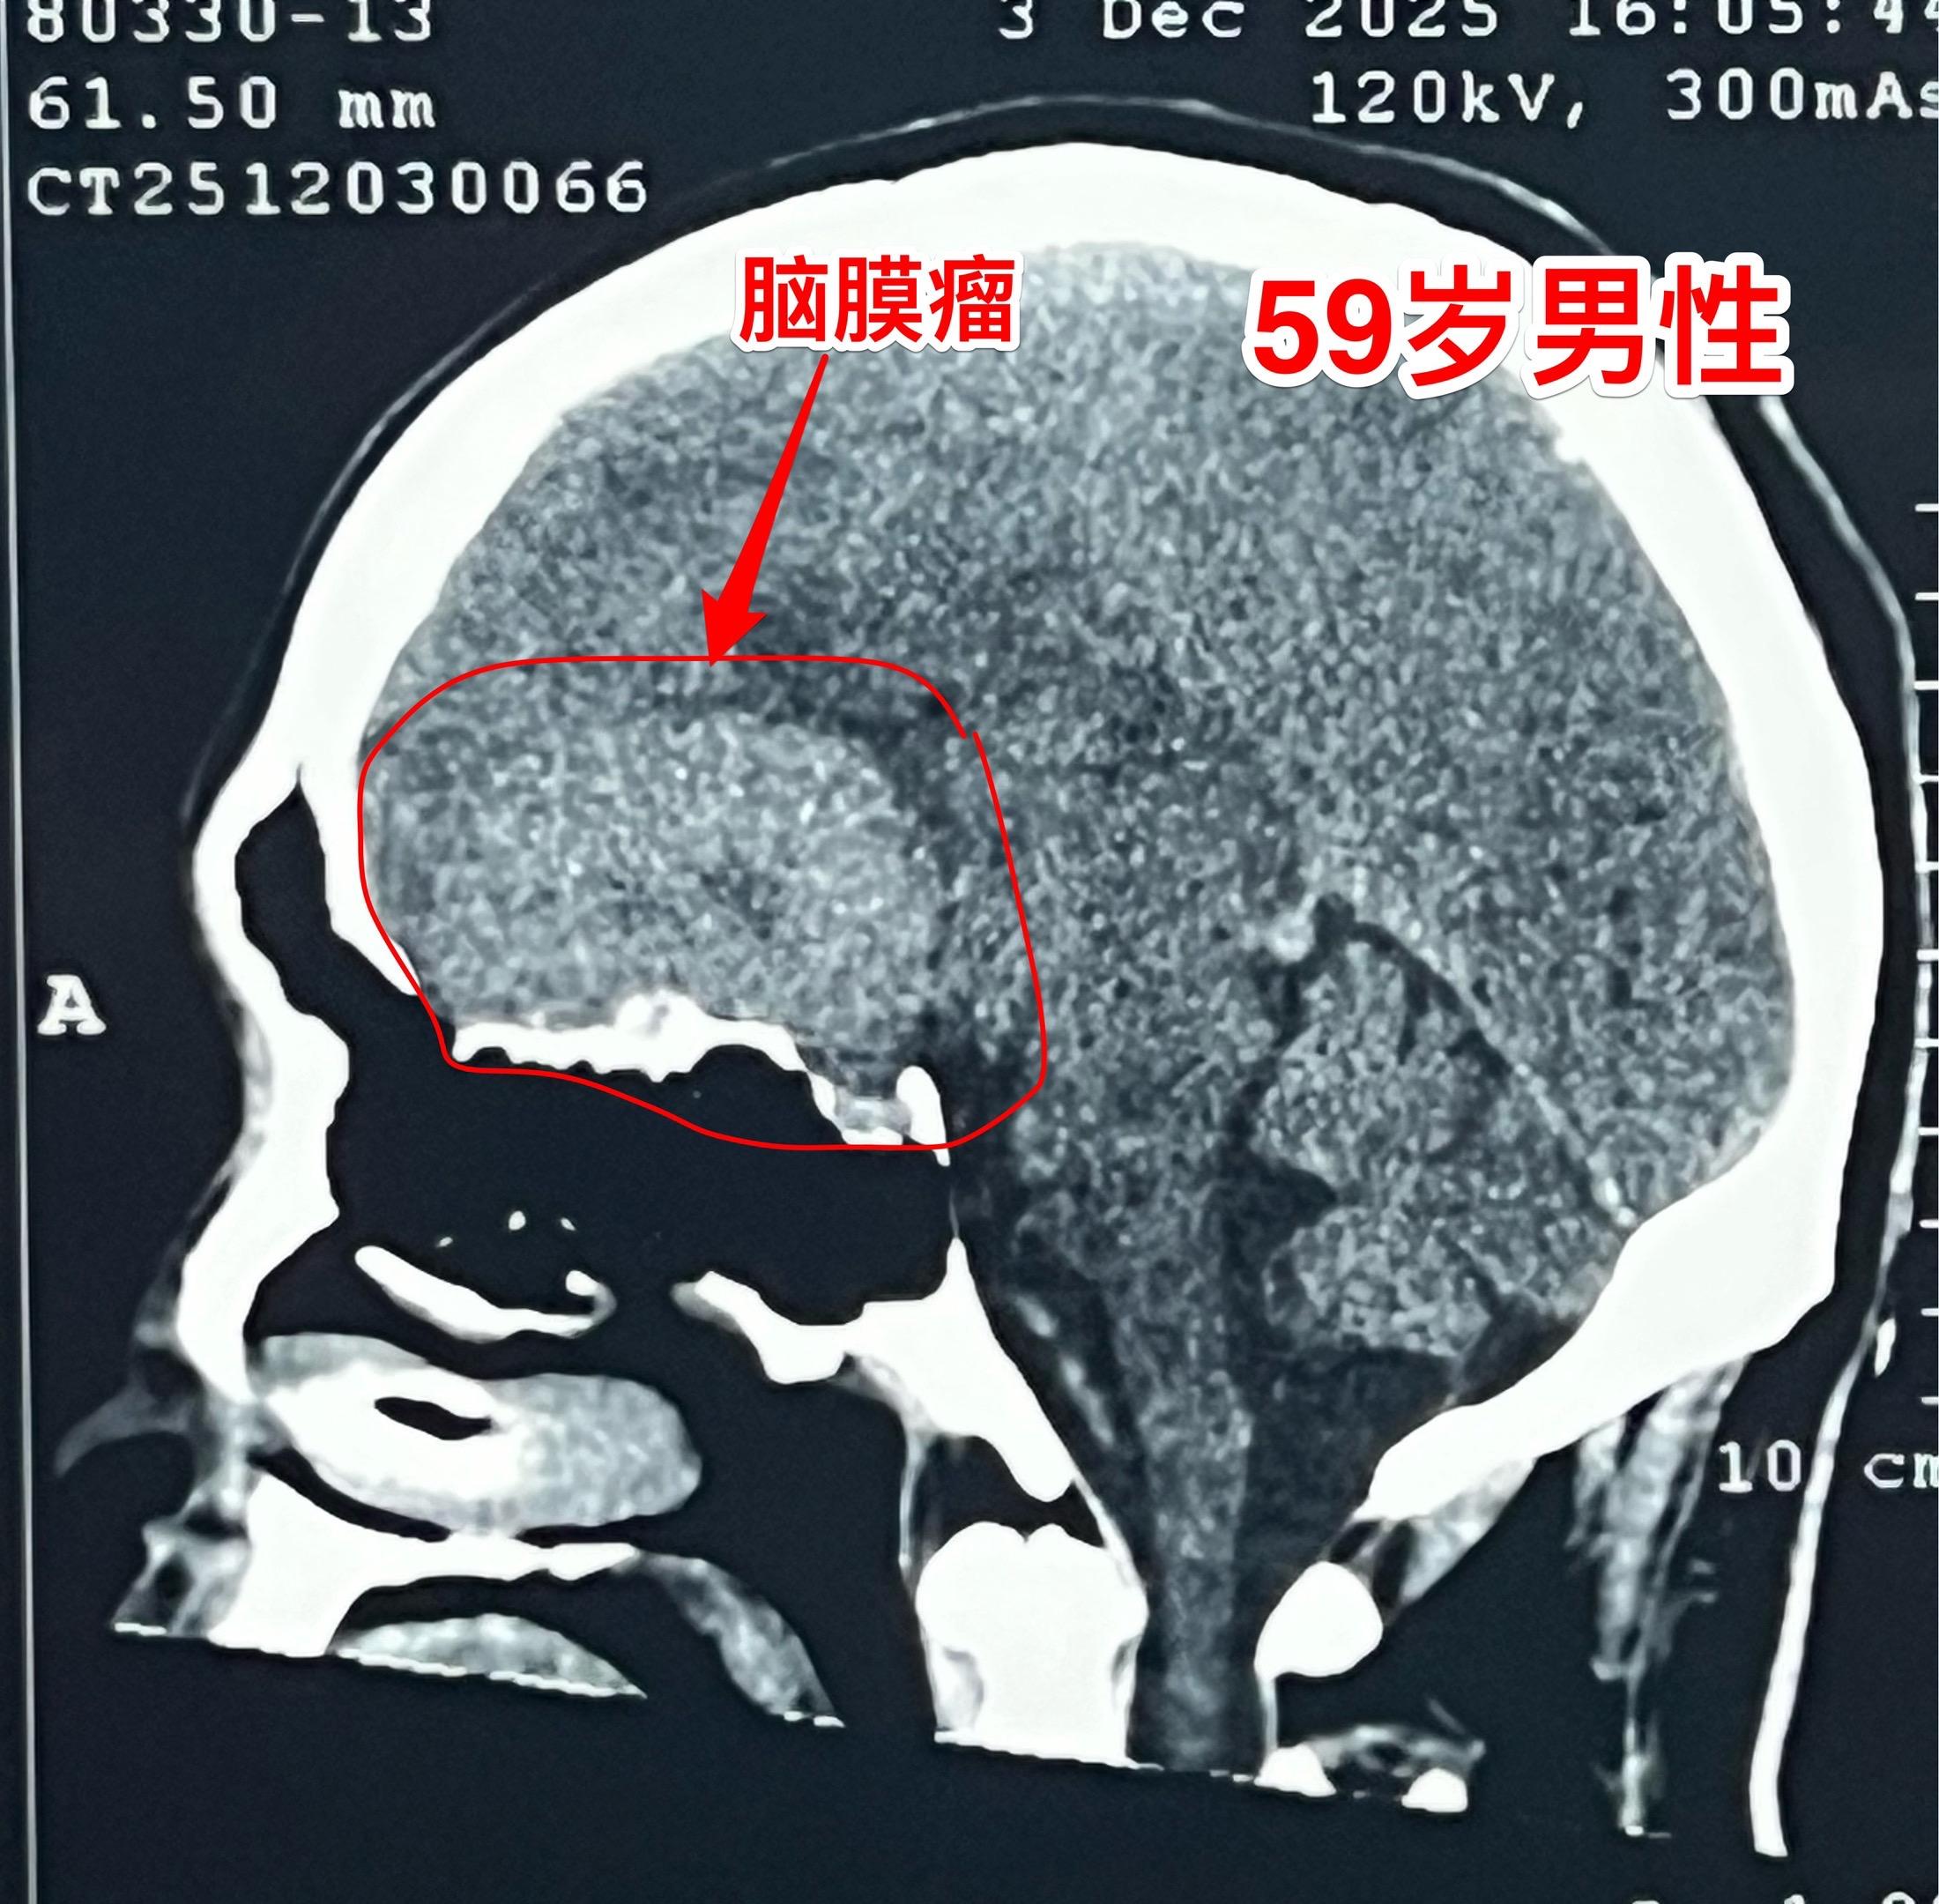

脑膜瘤长在不同的部位产生的症状也不同!这个59岁的内蒙古男性,最开始的症状是右眼视力下降,他认为与糖尿病有关,没有作详细检查。今年出现头痛症状,后来又出现左腿无力症状,他自认为是脑梗塞。症状越来越严重,还发现了嗅觉丧失症状。医生建议行脑部磁共振检查,作了磁共振之后就发现了这个巨大肿瘤。 这个脑膜瘤位置靠近嗅神经、视神经,所以导致视力下降和嗅觉丧失,同时肿瘤导致右侧大面积的脑水肿,造成左腿无力。手术后这些症状有望好转。